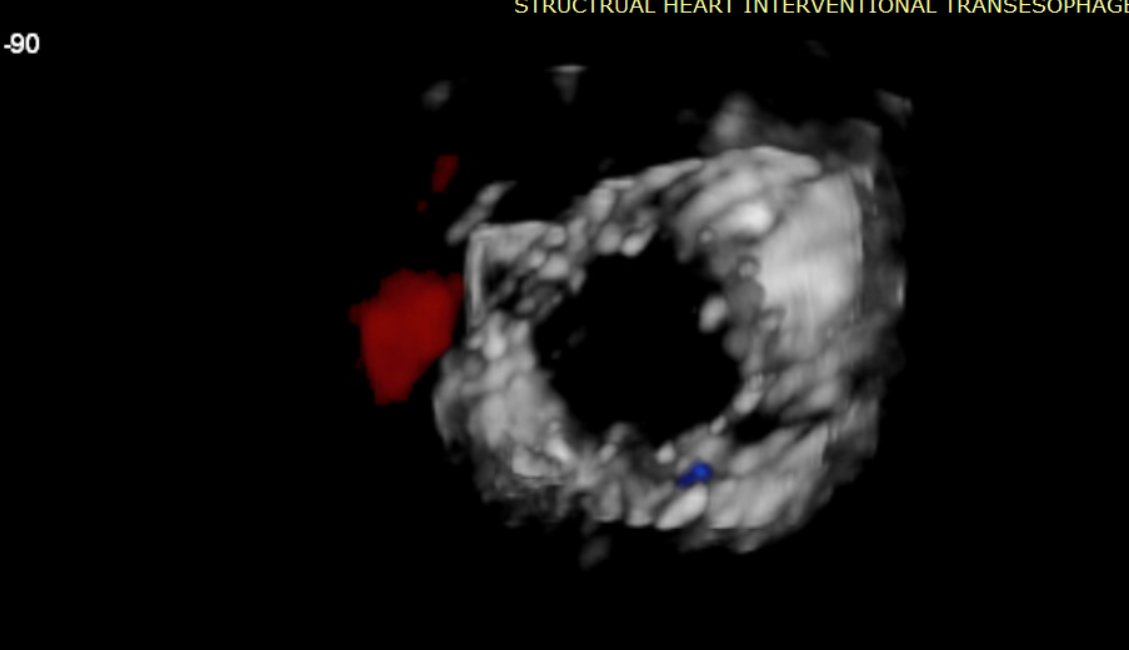

術(shù)前超聲提示大量三尖瓣反流

術(shù)后超聲提示無瓣周漏